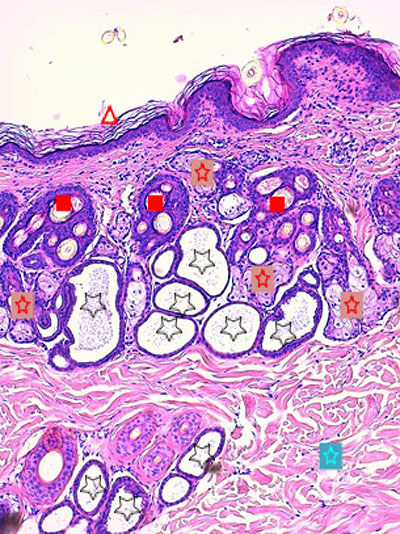

Légendes de la Photo 3 :

- Pointe de flèche rouge = hyperkératose orthokératosique de l’épiderme

- Étoile turquoise = derme périannexiel non inflammatoire hormis en zone péri-isthmique

- Étoile rouge = glandes sébacées plurilobulées hyperplasiques

- Carré rouge = portions infundibulaires et isthmiques des follicules pileux : la gaine épithéliale folliculaire externe est hyperplasique

- Étoile noire = lumière kystique des glandes sudorales épitrichiales

Légendes de la Photo 4 :

- Pointe de flèche rouge = tige pilaire dans isthme folliculaire

- Étoile rouge = fundus de glande sudorale épitrichiale

- Étoile turquoise = lobules de glande sébacée hyperplasique

- Flèche double noire = canal sébacé hyperplasique et hyperkératosique (orthokératose)

- Carré rouge = follicule pileux en phase anagène

- Étoile rouge = infiltrat inflammatoire lympho-plasmocytaire péri-isthmique